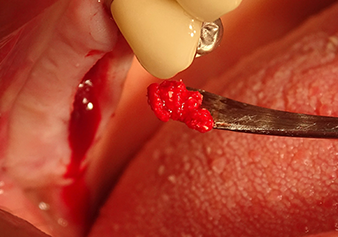

Lo strumento I2A (diametro 2,0 mm) è stato quindi impiegato per perforare il pavimento sinusale in modo graduale e su superfici molto ridotte. Tale metodo piezochirurgico previene il danneggiamento della membrana di Schneider. Durante l'utilizzo di Z25P, la membrana risultava già essere leggermente sollevata dal fluido di raffreddamento fornito attraverso la punta dello strumento (Fig. 3). La quantità di fluido di raffreddamento presente era solo del 50% per evitare che la sede dell'impianto registrasse un'elevata pressione.

Preparazione e accrescimento della sede dell'impianto

Dopo un controllo intermedio (Fig. 4) è stata eseguita un'ulteriore fase di preparazione (Fig. 5). Lo strumento idraulico Z35P è stato utilizzato in un secondo momento per sollevare la membrana sino alla posizione desiderata (Fig. 6 e 7). In seguito alla suddetta operazione, si è proceduto ad una ulteriore preparazione piezochirurgica della sede dell'impianto conclusasi con l'applicazione della fresa e della fresa a spallamento sul diametro dell'impianto di 4,8 mm. Il materiale di rinforzo (dimensione delle particelle di ca. 0,8 - 1,6 mm) è stato introdotto sotto la membrana di Schneider prima che venisse inserito l'impianto (Fig. 8).